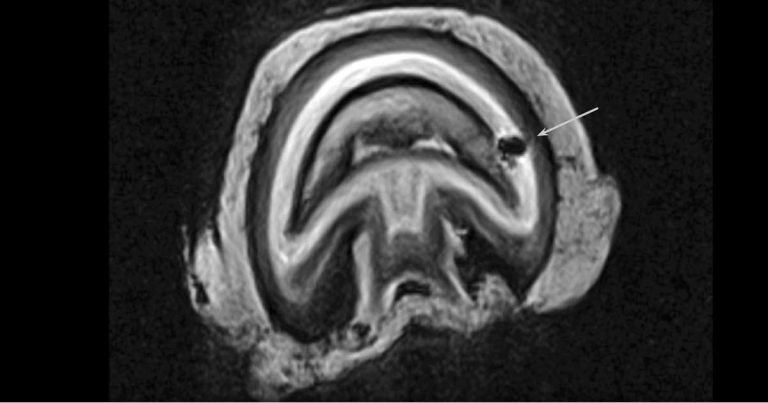

On MRI, septic pedal osteitis will appear as a focal area of hyperintensity on T2-weighted images, extending into the distal phalanx, while on T1-weighted images the area can appear hypointense within subchondral bone (Figure 3), which is consistent with bone sclerosis (Mizobe et al, 2017).

If the cause of the osteitis is a penetrating trauma, a signal void may appear to outline a tract to the distal phalanx. Increased signal intensity will also be visible in fat‑suppressed images, which may be coupled with irregularity of the cortical bone and disruption of adjacent laminae, which is evidence of an active osteitis (Dyson, 2011a).